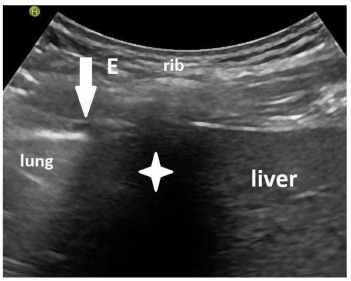

Methods: 84 patients were included when they were able to breathe at least 10 minutes over a t-piece and sit upright for at least 5 minutes. The diaphragmatic function was estimated sonographically using the up and downward movement of the lung silhouette. Sonographic follow-ups were performed for over 18 months. The survival rate, outcome and changes in diaphragm mobility were investigated.